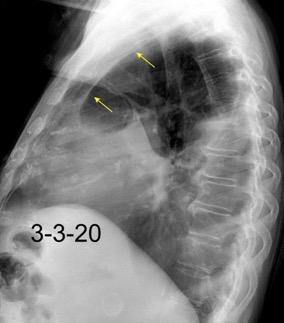

Marzo 2014: Perforación longitudinal distal secundaria a episodio de vómito (síndrome de Boerhaave). Derrame pleural izdo. que evoluciona a empiema.

Wang C-T et al. Tension hydropneumothorax in a Boerhaave syndrome patient: A case report . World J Emerg Med, 2021. Katabathina V et al. Nonvascular, nontraumatic mediastinal emergencies in adults:a comprehensive review of imaging findings. Radiographics. 2011.